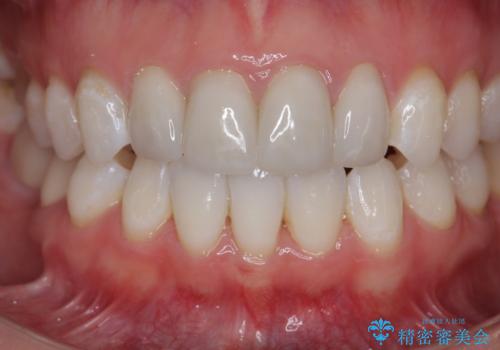

仮歯のまま放置していた前歯をセラミックに

- 仮歯のまま放置してしまい、変色を改善しきれいなセラミッククラウンをいれたい、と希望され来院されました。

特に虫歯の再発や神経の症状等問題を認めなかったので、審美的に優れるセラミッククラウンに仮歯を置き換えていきます。

- 52.8万円(ジルコニアクラウン×4・仮歯×4)費用は治療当時の料金となります